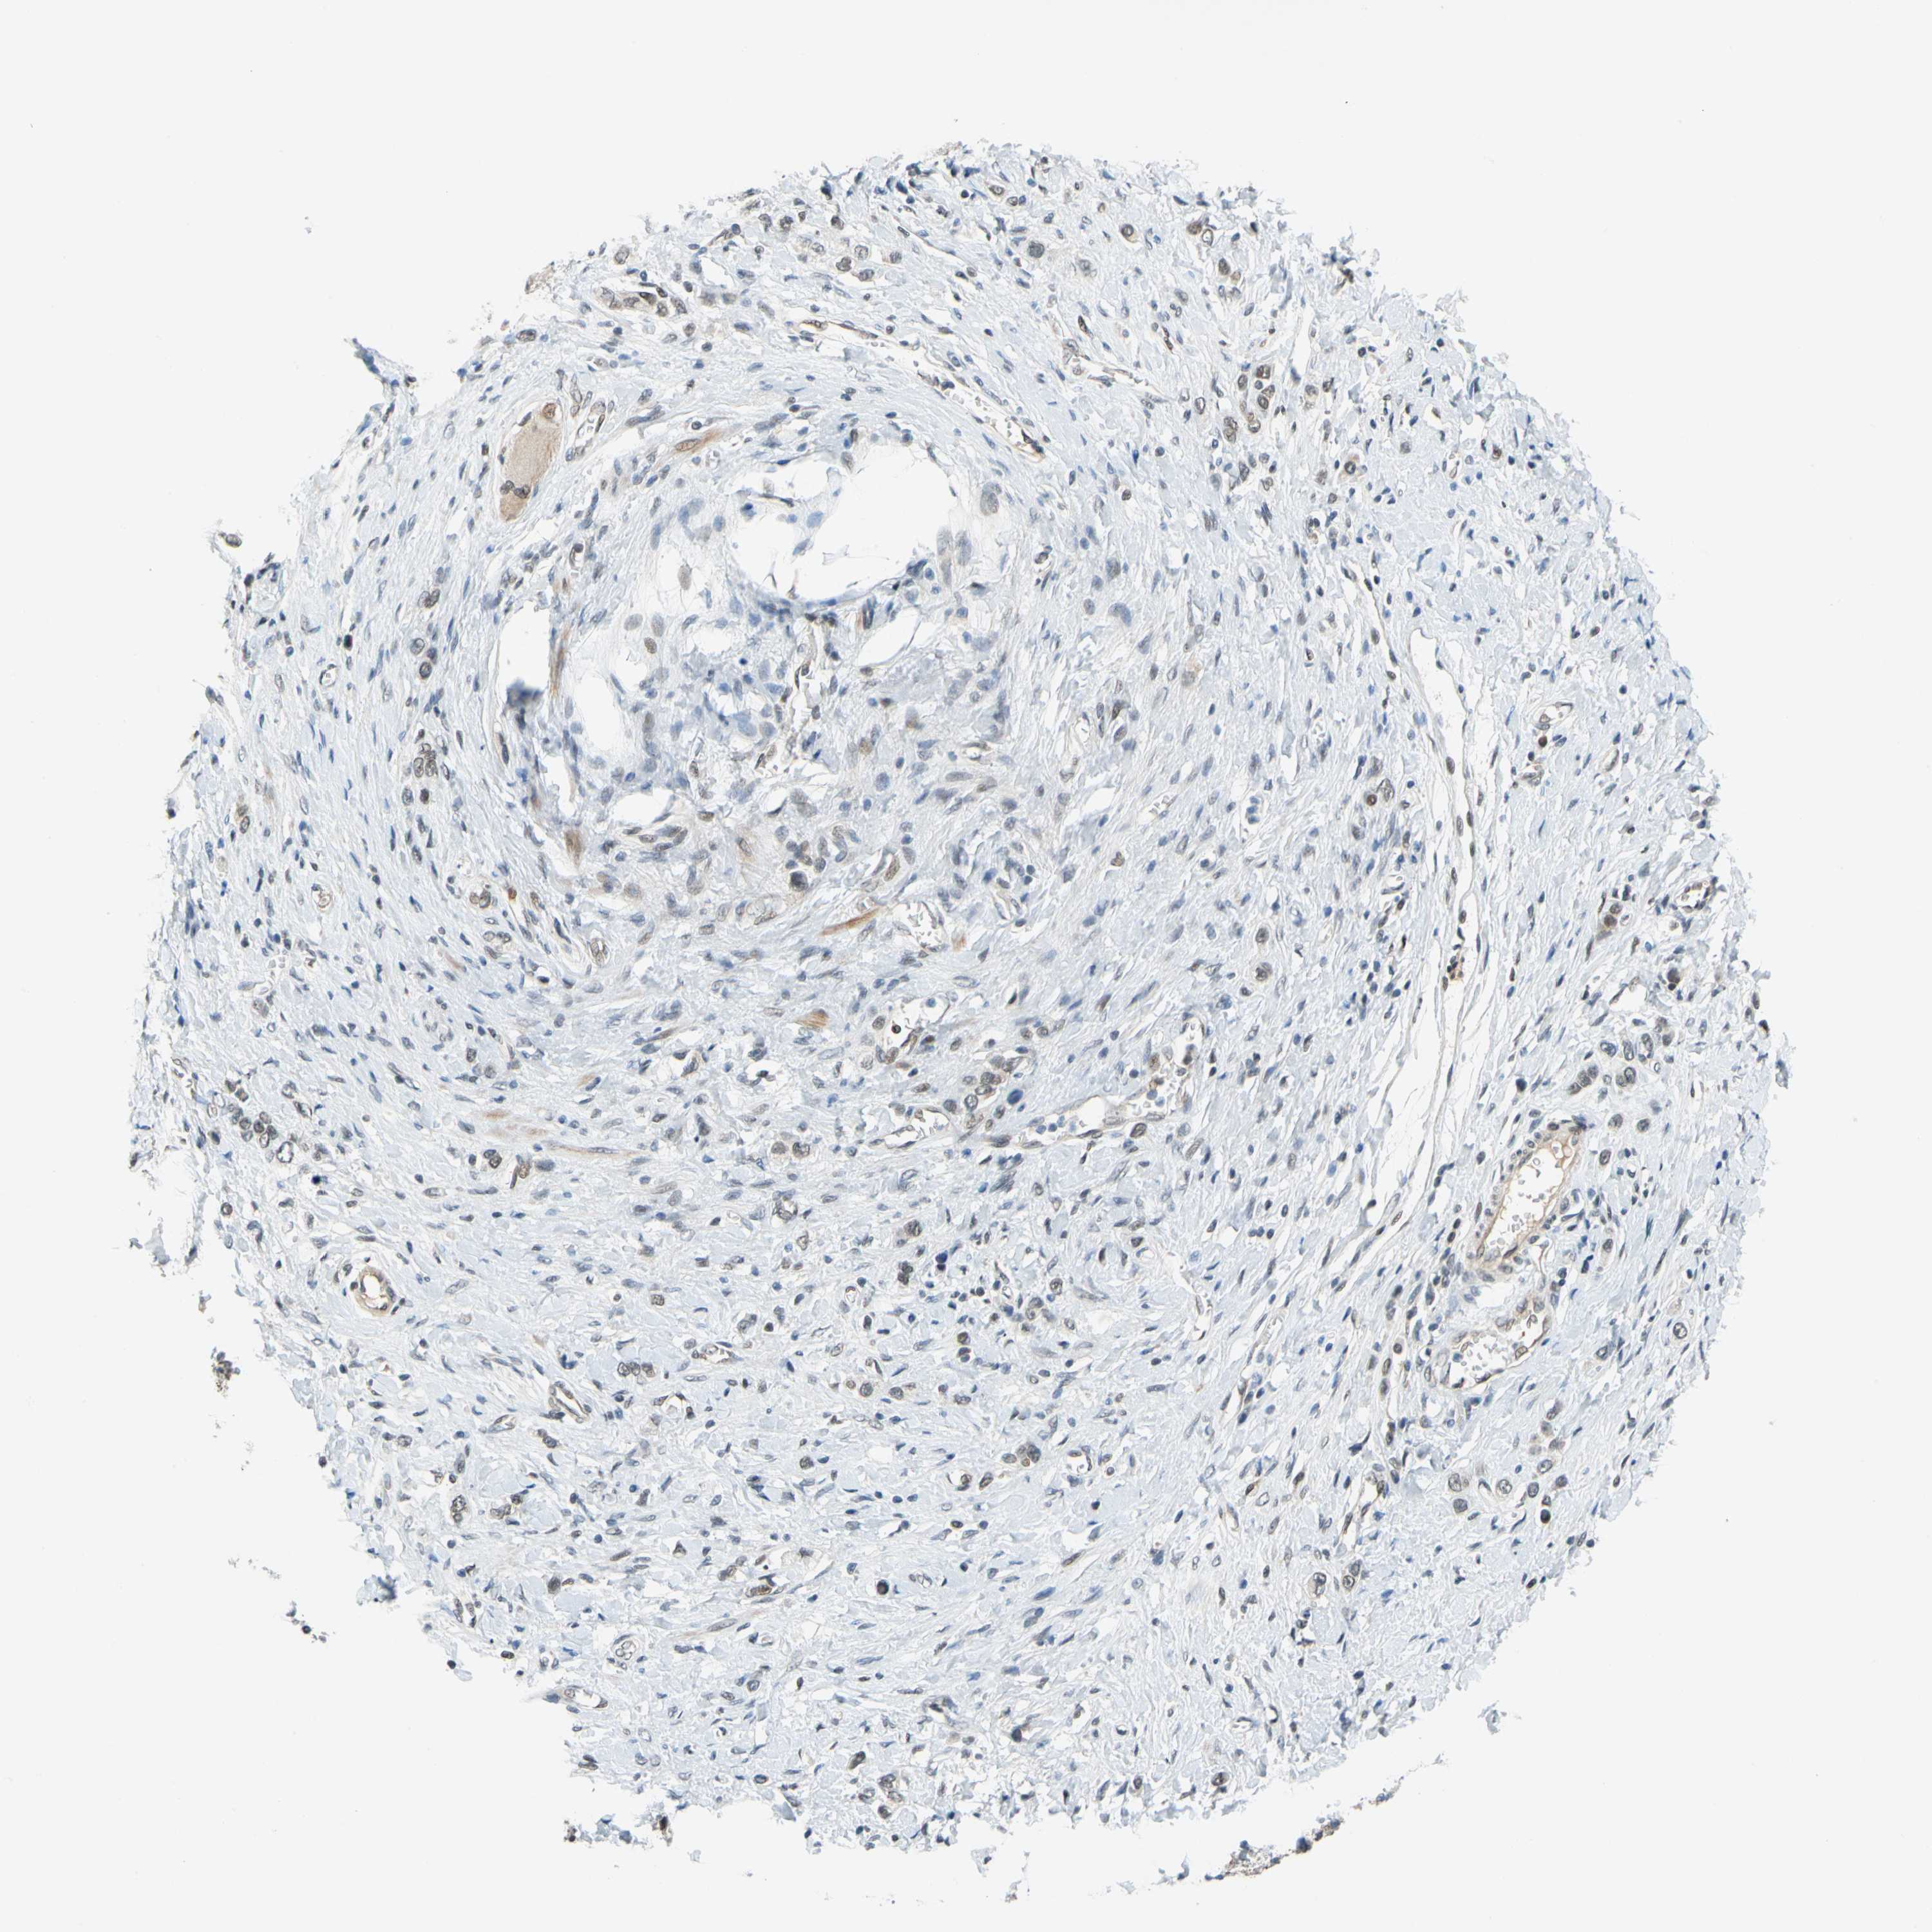

STOMACH CANCER - Protein expressioni

A mouse-over function shows sample information and annotation data. Click on an image to view it in a full screen mode. Samples can be filtered based on level of antibody staining by selecting one or several of the following categories: high, medium, low and not detected. The assay and annotation is described here.

Note that samples used for immunohistochemistry by the Human Protein Atlas do not correspond to samples in the TCGA dataset.

Antibody stainingi

Antibody staining in the annotated cell types in the current human tissue is reported as not detected, low, medium, or high, based on conventional immunohistochemistry profiling in selected tissues. This score is based on the combination of the staining intensity and fraction of stained cells.

Each image is clickable and will lead to virtual microscopy that enables deeper exploration of all samples and also displays staining intensity scores, fraction scores and subcellular localization as well as patient and tissue information for each sample.

Antibody HPA006800

Antibody HPA008781

Staining

High

Medium

Low

Not detected

Intensity

Strong

Moderate

Weak

Negative

Quantity

>75%

75%-25%

<25%

None

Location

Nuclear

Cytoplasmic/membranous

Cytoplasmic/membranous,nuclear

Adenocarcinoma, NOS